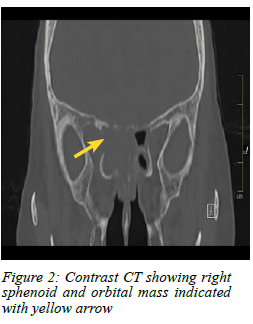

A computed tomography (CT) scan of the brain and paranasal sinuses showed a mass lesion in the right parasellar region and orbital apex with extension into the sphenoid sinus (Figure 1 and 2).

The diagnostic algorithm includes a full physical examination and imaging. CT scan of the brain and paranasal sinus is the primary imaging modality of choice as it can demonstrate a mass in the orbit. Magnetic resonance imaging (MRI) scans help delineate the mass from the surrounding soft tissue structures.2-49 In our patient, MRI was not performed as the CT scan clearly delineated the pathology and site.

Blindness and ophthalmoplegia from breast cancer metastases to the orbital apex and sphenoid sinus after a 10-year disease-free interval is very rare. Involvement of the optic nerve differentiates this presentation from other forms of ophthalmoplegia found in the superior orbital fissure and cavernous sinus syndrome. A high-resolution CT scan is often sufficient to delineate the location and extent of the disease, and guide biopsy which is necessary to determine the aetiology and origin of the disease. A PET scan is used for oncological staging and to guide appropriate treatment. Prognosis for orbital metastasis of breast cancer is poor with an average survival of 31 months.4